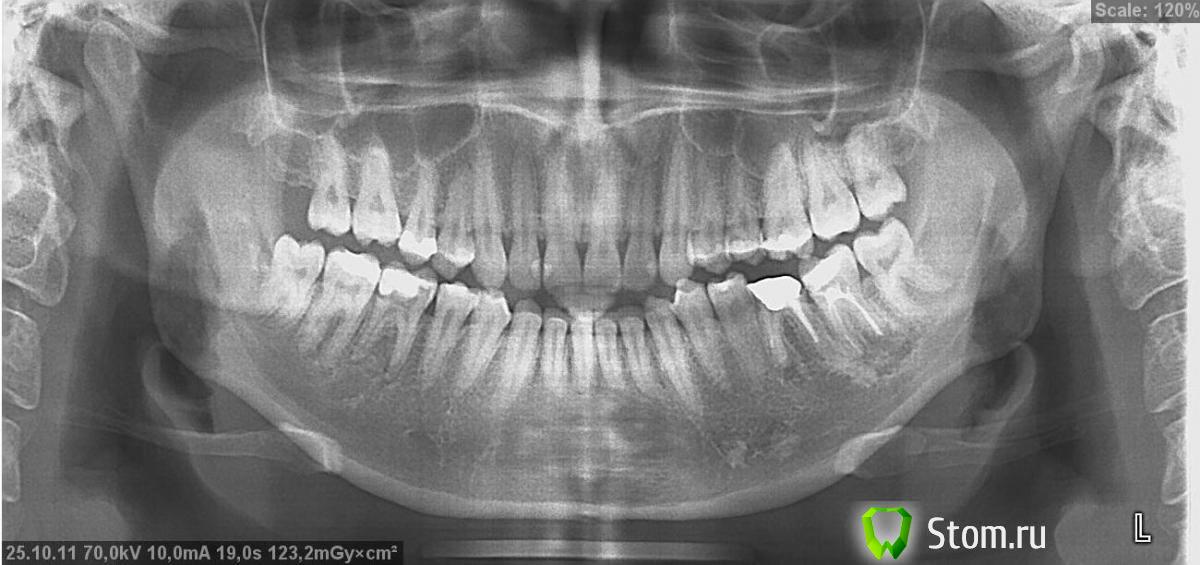

Татьяна 89 Опубликовано 11 января, 2012 Поделиться Опубликовано 11 января, 2012 здравствуйте! у меня вопрос: если удалить зуб мудрости (48) - не "поедут" ли вправо остальные зубы нижней челюсти, стремясь заполнить образовавшееся пустое место?на этом зубе уже есть средний кариес, его (зуб) практически невозможно качественно почистить (остальные восьмёрки легко поддаются чистке). возможно, эта информация имеет какое-то значение: зубы мудрости прорезались в 15 лет, не доставляя никакого дискомфорта, безболезненно и довольно быстро. 16 зуб удален в 11 лет. сейчас мне 22 года. Ссылка на комментарий

Elenushka Опубликовано 12 января, 2012 Поделиться Опубликовано 12 января, 2012 на нижней челюсти зубы плохо двигаются да же если там стоят брекеты.я вам советую купить ирригатор и детскую зубную щетку я восьмеры ею вычищаю. там у вас 36 требует вниманияудалить всегда успеете, не торопитесь.тем более дист бугор прикрыт костью.Не всегда удаление зубов бывает не травматичным Ссылка на комментарий

Татьяна 89 Опубликовано 12 января, 2012 Автор Поделиться Опубликовано 12 января, 2012 (изменено) на нижней челюсти зубы плохо двигаются да же если там стоят брекеты.я вам советую купить ирригатор и детскую зубную щетку я восьмеры ею вычищаю. там у вас 36 требует вниманияудалить всегда успеете, не торопитесь.тем более дист бугор прикрыт костью.Не всегда удаление зубов бывает не травматичныместественно, я в курсе ситуации и с 36, и с 37, и с 46. снимок был сделан ещё в октябре. в данный момент меня интересует именно этот зуб мудрости. "тем более дист бугор прикрыт костью"и что? это на что-то влияет? "Не всегда удаление зубов бывает не травматичным"конечно, нужно быть готовым ко всему. но абы-к-какому хирургу я не пойду, чтобы лишний раз не рисковать. Изменено 12 января, 2012 пользователем Татьяна 89 Ссылка на комментарий

Татьяна 89 Опубликовано 12 января, 2012 Автор Поделиться Опубликовано 12 января, 2012 а на мой взгляд лучше бы удалить. Bier, спасибо! согласна с Вами.не думаю, что есть смысл его лечить. да и места в челюсти ему явно не хватает. ведь больше он уже не прорежется, так? и хотелось бы ещё раз у Вас уточнить: не начнут ли постепнно перемещаться (и тем самым увеличивая межзубные промежутки) вправо остальные зубы? Ссылка на комментарий

Force Опубликовано 15 января, 2012 Поделиться Опубликовано 15 января, 2012 Да, у вас корпусно (с корнем) лишь небольшой наклон. Ссылка на комментарий